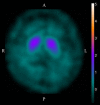

- Booth, T. C. , Nathan, M. , Waldman, A. D. , Quigley, A. M. , Schapira, A. H. , & Buscombe, J. (2015a). The role of functional dopamine‐transporter SPECT imaging in parkinsonian syndromes, part 1. AJNR. American Journal of Neuroradiology, 36(2), 229–235. https://doi.org/10.3174/ajnr.A3970 - DOI - PMC - PubMed

- Booth, T. C. , Nathan, M. , Waldman, A. D. , Quigley, A. M. , Schapira, A. H. , & Buscombe, J. (2015b). The role of functional dopamine‐transporter SPECT imaging in parkinsonian syndromes, part 2. AJNR. American Journal of Neuroradiology, 36(2), 236–244. https://doi.org/10.3174/ajnr.A3971 - DOI - PMC - PubMed